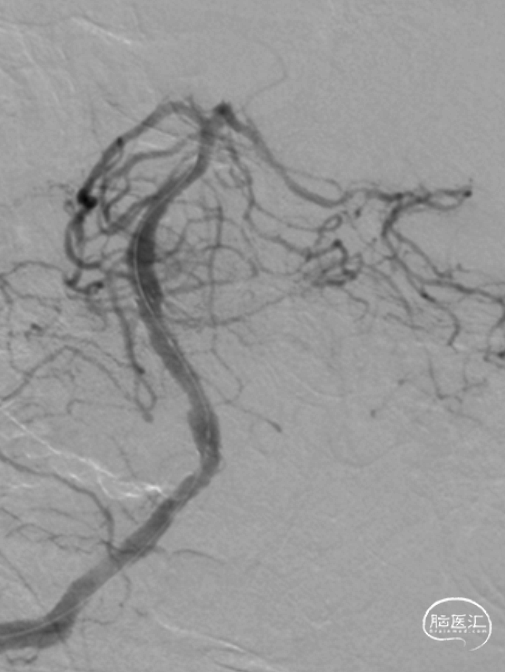

右侧桡动脉穿刺造影:右侧椎动脉优势;左侧椎动脉发自弓上,纤细迂曲;双侧后交通动脉欠发达。

超选右侧椎动脉造影:右侧椎-基底动脉连接处次全闭塞,前向血流 mTICI 2b级。

气管插管全麻。6F 指引导管、5F多功能管、泥鳅导丝同轴,将指引管放置于右侧椎动脉V2段。路径图下,将Synchro-14 微导丝引导SL-10微导管导管小心通过椎基底动脉次全闭塞处,放至右侧大脑后动脉P1段。更换为Trensend-300cm微导丝,撤出SL-10微导管。

分别应用2.5mm×15mm、3.25mm×15mm球囊,仔细定位后,以6ATM命名压缓慢扩张。